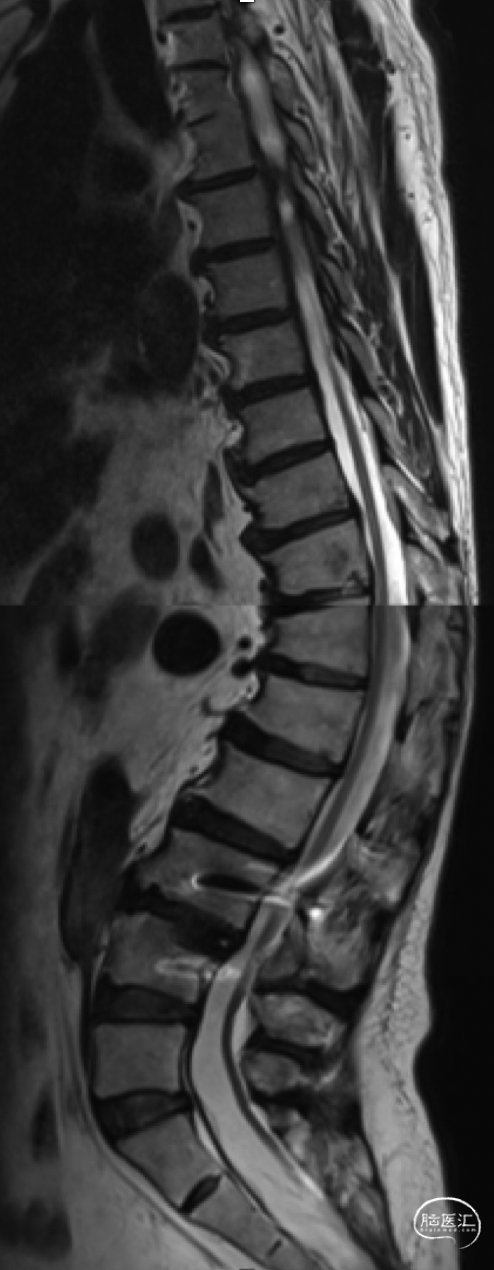

本次术前CT

本次术前MR